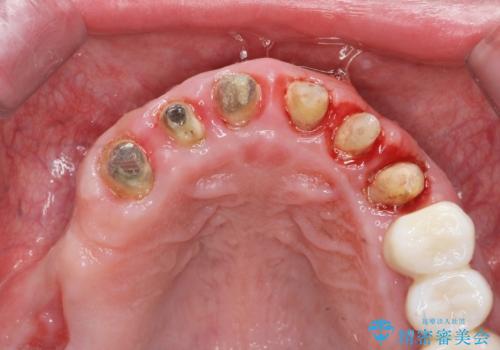

- 前医で行った前歯セラミック形態の改善、常に腫れぼったく歯ブラシの際に出血のある前歯部の治療を希望され来院されました。

前医により、前歯は歯ぐきの奥深くまで形成されこのままの状態でセラミックをやりかえたとしても歯ぐきの腫れの改善は難しい状況です。

歯周外科を行い歯と歯槽骨・歯肉の関係を是正することで歯ぐきの状態を改善し、将来に亘り安定した歯周環境の維持を期待できるセラミック治療を実践します。